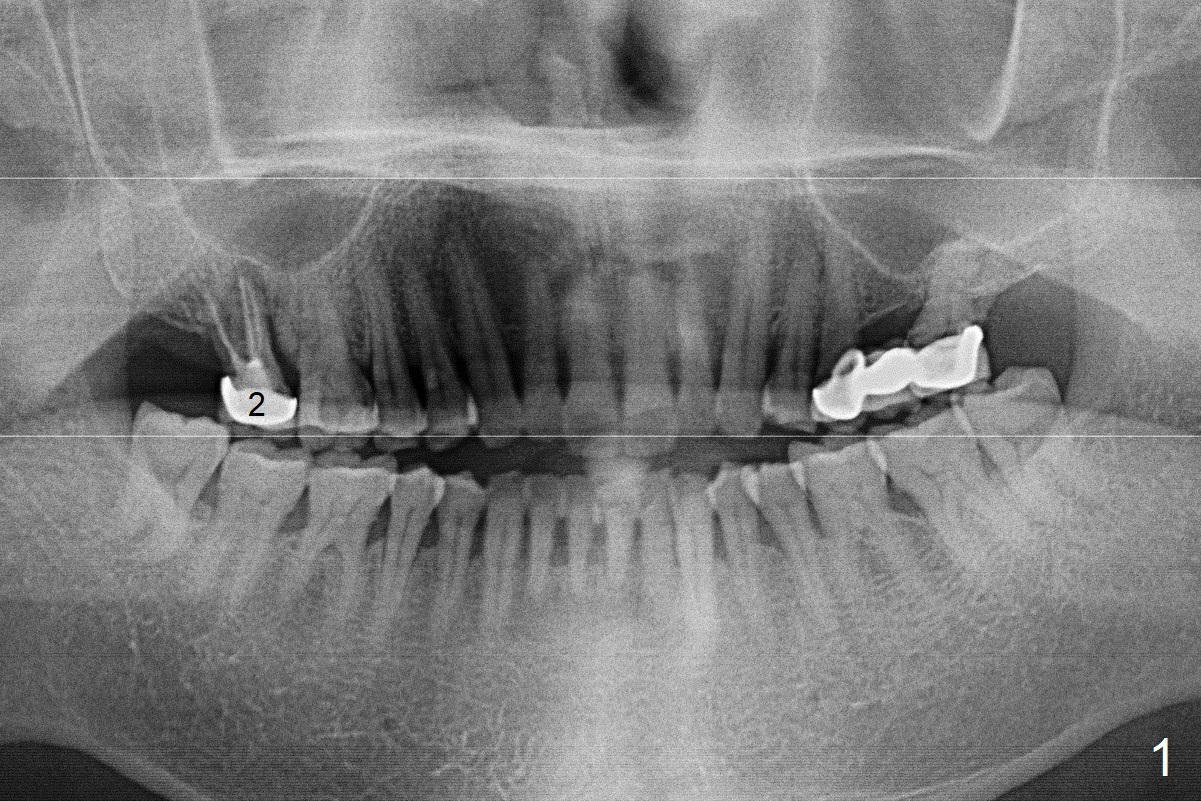

A 65-year-old man returned to finish LR and LL quadrant SRP a few weeks post SRP for UR quadrant and #2 extraction (Fig.1-2). He returns for UL SRP tomorrow ~ 3 months post extraction (Fig.4). Although the patient cannot remember whether socket preservation is done or not, there appears to be bone graft in the socket. The ridge is wide. It seems reasonable to expand and condense the socket using Magic Split and Expanders (flapless). If the patient cannot tolerate tapping, use DIO Bone Expanders. A 6.5x9 (3) mm Magicore will be placed (Fig.5,6).